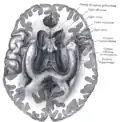

Base of brain (Tuber cinereum visible at center).

The tuber cinereum is the portion of hypothalamus forming the floor of the third ventricle situated between the optic chiasm, and the mammillary bodies.[1][2] The tuberal region is one of the three regions of the hypothalamus, the other two being the chiasmatic region and the mamillary region.[1]

The tuber cinereum is a convex mass of grey matter,[3]: 495  a ventral/inferior distention of the hypothalamus forming the floor of the third ventricle. The portion of the tuber cinereum at the base of the infundibulum (pituitary stalk) is the median eminence;[2] the infundibulum extends ventrally/inferiorly from the median eminence to become continuous with the infundibulum.[3]: 499

The tuber cinereum is situated caudal to the optic chiasm, medial to the optic tract (which flanks it on either side), and rostral to the two mammillary bodies.[4] is continuous anteriorly with the lamina terminalis, and laterally with the anterior perforated substances.